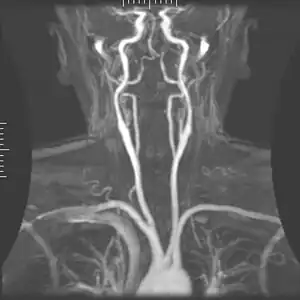

Angiography

Magnetic resonance angiography

Magnetic resonance angiography (MRA) generates pictures of the arteries to evaluate them for stenosis (abnormal narrowing) or aneurysms (vessel wall dilatations, at risk of rupture). MRA is often used to evaluate the arteries of the neck and brain, the thoracic and abdominal aorta, the renal arteries, and the legs (called a "run-off"). A variety of techniques can be used to generate the pictures, such as administration of a paramagnetic contrast agent (gadolinium) or using a technique known as "flow-related enhancement" (e.g., 2D and 3D time-of-flight sequences), where most of the signal on an image is due to blood that recently moved into that plane (see also FLASH MRI).[39]

Techniques involving phase accumulation (known as phase contrast angiography) can also be used to generate flow velocity maps easily and accurately. Magnetic resonance venography (MRV) is a similar procedure that is used to image veins. In this method, the tissue is now excited inferiorly, while the signal is gathered in the plane immediately superior to the excitation plane—thus imaging the venous blood that recently moved from the excited plane.[40]